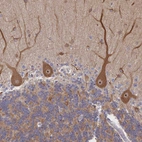

Immunohistochemical staining of human cerebellum shows strong cytoplasmic positivity in Purkinje cells.